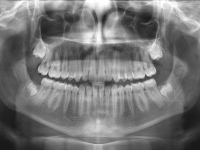

El paciente E.A. acude a nuestra consulta por diastema inferior y ausencia de contactos en los sectores laterales.

Chica de 17 años tratada en 1 año con stripping en los dientes inferiores